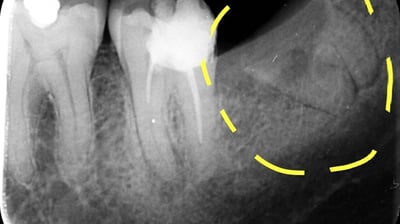

Radiografii retroalveolare

Aceste radiografii sunt utilizate pentru a evalua structurile osoase ale maxilarelor și mandibulei, fiind utile în special pentru tratamente ortodontice sau implanturi dentare.